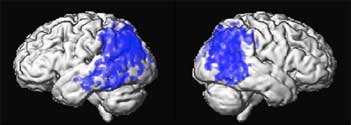

Decreased metabolism in AD compared to controls

Positron emission tomography scans of 6 patients with Alzheimers disease

showing areas of decreased glucose utilization before surgery in

blue which are reversed with DBS after 1 month or 12 months of DBS.

Restoring glucose utilization suggests that these brain areas that were shut

down are once again active.